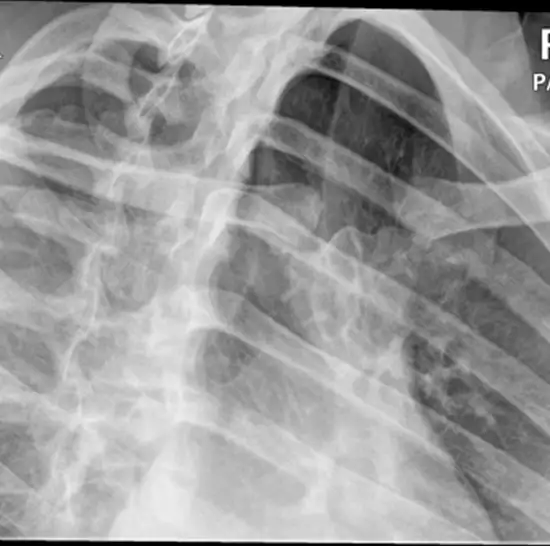

X-ray Left Sterno Clavicular Joint PA Oblique

It is safe and painless to take an X-ray of the sternoclavicular joint, where the collar bone connects to the breastbone and the first rib. It also helps to picture the skin and muscles close to it.